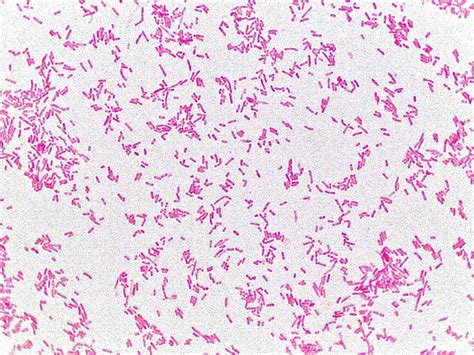

🔍 Note: Proper staining techniques are essential for distinguishing *E. coli* from other bacteria. Gram staining is commonly used, where *E. coli* will appear pink or red due to its gram-negative nature.

When viewed under a microscope, *E. coli* exhibits several distinctive features:

• Shape: *E. coli* is a rod-shaped bacterium, typically appearing as short, straight rods.

• Size: The cells are relatively small, usually measuring about 2.0 µm in length and 0.5 µm in diameter.

• Staining: As a gram-negative bacterium, *E. coli* will stain pink or red with Gram staining.

• Motility: Some strains of *E. coli* are motile and can be observed moving using a phase-contrast microscope.

These features are crucial for identifying *E. coli* under a microscope and differentiating it from other bacterial species.